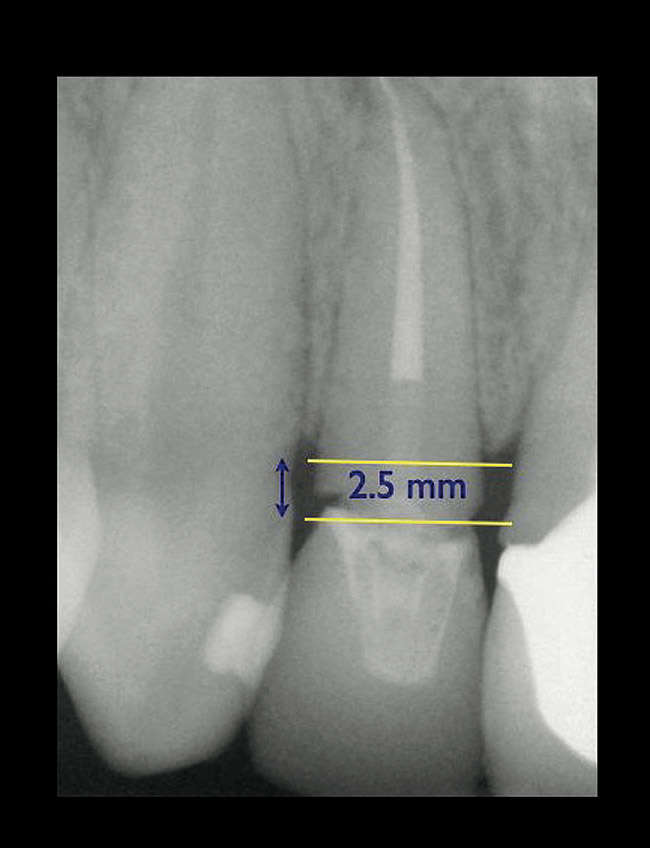

If the tooth has been endodontically treated, the remaining tooth structure relative to the post space needs to be evaluated. The Rule of Thirds is used in this situation. It states that the canal or canal space preparation should not be any wider than one third the mesiodistal root diameter after the endodontic access (Figure 3).3 Once the clinician determines whether adequate tooth structure is present, the second area to evaluate is the distance of the fracture/caries from the crest of bone. To avoid biological width impingement, the minimum distance needed from the osseous crest to the final margin placement is 2.5 mm (Figure 4). As determined in cadaver studies, this consists of approximately 1 mm of connective tissue attachment, 1 mm of junctional epithelium, and 0.5 mm of gingival sulcus.4 This measurement is meant as a guideline and not an absolute number, as it has been shown to have individual variability.5 This actual dimension for the individual patient can be predictably determined by sounding to bone on the adjacent teeth to more closely determine the individual’s biologic width.6